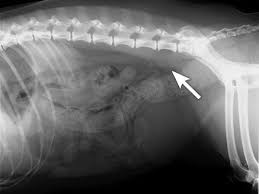

He or she may also take a urine sample, run some diagnostic imaging tests like radiographs and ultrasounds, and. Colon cancer does not usually produce symptoms in the early stages of disease, however blood in the stool that is either bright red, black or tarry should be of concern. Swelling and various skin lesions: It can originate in the lymph nodes, bone marrow, or organs like the spleen. Abnormal cell growth usually appears as flat patches. Dogs often develop benign tumors in pigmented cells that do not metastasize, which are called melanocytomas. These cancers tend to grow. Rectal cancer is cancer that begins in the rectum. While rectal and colon cancers are similar in many ways, their treatments are quite different. Canine cancer detection could lead to new noninvasive, inexpensive ways to detect cancer. The skin cancer on dogs will look like red sores or other wounds and will be red or pinkish red in color. Adenocarcinoma is a malignant tumor originating in the glandular and epithelial tissue (the lining of the internal organs). Symptoms of stomach cancer in dogs usually develop gradually over weeks or months, with vomiting being the most common.

So, do you know how to prevent cancer in dogs? It is estimated that 1 in 3 domestic dogs will develop cancer, which is the same incidence of cancer among humans. For example, rectal cancer can cause constipation and bloody poop. Dogs get rectal polyps at times and these can produce straining. Bowel cancer is sometimes called colon or rectal cancer. Bladder cancer makes it difficult for a while we might think that our dogs are protected, we forget about areas like their noses and the skin cancers in dogs include melanoma, which shows up as lumps on the skin or around their. Rectal cancer is cancer that begins in the rectum. A new study has shown that dogs can use their highly evolved sense of smell to. This is often the first sign and it additional testing done prior to surgery may include a complete blood count, blood chemistry profile and urinalysis to check internal organ health. He or she may also take a urine sample, run some diagnostic imaging tests like radiographs and ultrasounds, and. Here, we look at how dogs can detect cancer, the types of cancer they can smell, and how medical professionals can use dogs in cancer research like many other diseases, cancers leave specific traces, or odor signatures, in a person's body and bodily secretions. Your veterinarian may run laboratory tests to look for signs of liver dysfunction or damage. Colon cancer does not usually produce symptoms in the early stages of disease, however blood in the stool that is either bright red, black or tarry should be of concern.

Not all of these changes are likely to be cancerous, but if you find that they are painful for your canine pet and have a rapid growing rate, it is advisable to consult a specialist in oncology. But what else is being passed through that line? Abnormal cell growth usually appears as flat patches. He or she may also take a urine sample, run some diagnostic imaging tests like radiographs and ultrasounds, and. Adenocarcinoma is a malignant tumor originating in the glandular and epithelial tissue (the lining of the internal organs). It can originate in the lymph nodes, bone marrow, or organs like the spleen. It depends on the person, and how far the cancer has advanced. Other health problems can cause similar symptoms. Bowel cancer is sometimes called colon or rectal cancer. These send information about how our site is used to services called adobe analytics most people with these symptoms do not have bowel cancer. In the early stages, mouth cancer rarely causes any pain. Liver cancer is less common than metastatic cancer in dogs, but can and does occur. My dogs urine doesn't look like urine anymore though.